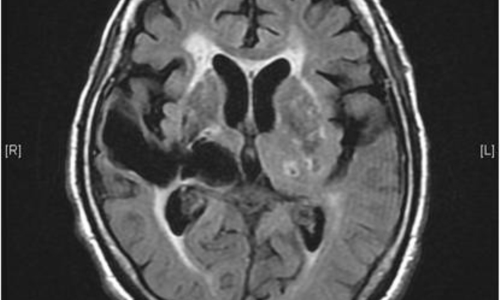

신체가 건강해도 뇌에 문제가 생기게 되면 신체 기능을 제대로 할 수가 없게 됩니다. 뇌 손상으로 제한된 신체 기능은 치료를 마친 후에도 회복이 제대로 되지 않거나 장애로 남는 경우가 많은데 뇌조직이 괴사되며 발생하게 되는 뇌경색이 대표적입니다. 과거에는 뇌출혈 환자가 많았지만 현재는 전체 뇌졸중 환자의 약 60~70%가 뇌경색 환자인 만큼 뇌졸중에서도 뇌경색이 차지하는 비중이 크다고 합니다.

건강보험심사평가원 자료에 따르면 뇌출혈로 병원을 찾은 환자보다 뇌경색으로 내원한 환자가 5배 이상 많았다고 하는데요 뇌경색은 뇌로 통하는 혈관이 막히면서 뇌 조직이 점차 괴사하게 되는 질환으로 날씨가 추워지는 겨울철에 특히 발생 가능성이 높은데요 혈관이 수축 하게 되면서 혈압 상승으로 이어지면서 뇌혈관 질환이 발생하게 되기 때문입니다.